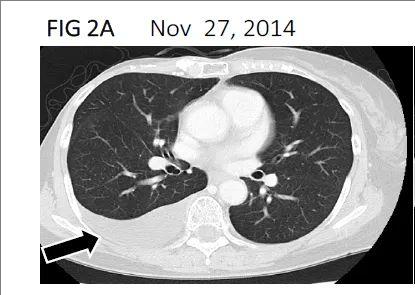

图1 该患者在治疗过程中影像学对比

▼2014年11月计算机断层扫描

注:影像学显示,右胸腔内有胸腔积液(黑色箭头)。